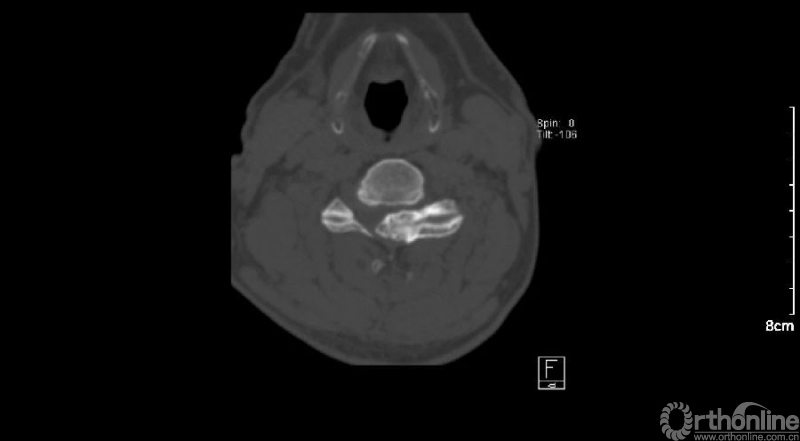

入院查体患者四肢肌张力高,双侧hoffman阳性。CT及MRI检查提示C4/5左侧关节突内缘有一巨大骨块(15mm*16mm),相应节段椎管严重狭窄。椎管内骨块的前端还有一游离骨块。

影像学资料